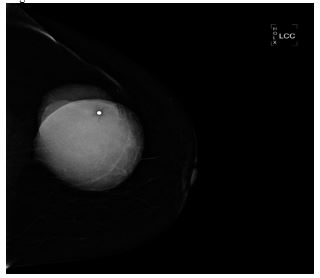

Alamer et al. [13] reported a 66-year-old lady who was known to have hypertension and diabetes mellitus who had presented with a palpable mass within her left breast that was associated with pain over a period of a long time. She did not have any nipple discharge or fever. She also did not have any history of breast trauma, hormone replacement therapy, or a family history of carcinoma of the breast. Her clinical examination showed a large palpable mass which was identified within her left breast with regular borders. Her nipple, areolar, and skin were normal. There was no evidence of palpable lymph node enlargement in her left axilla. Her general examination, systemic examinations and examination of her right breast and right axilla were normal. The results of her investigations including haematology blood tests, biochemistry blood tests, and chest x-ray were normal except elevated serum glucose result. She had a mammogram which showed a large oval and dense mass in the upper outer quadrant of her left breast (see figures 11 and 12). The mass was noted to be lobulated and well-circumscribed in its contours and to have measured 9.2 cm x 7.5 cm. No microcalcification was noted. The nipple, areolar, and skin were normal. The axillary lymph nodes were normal and the right breast was normal. Based upon the mammography examination features of the lump an impression of an usual large dense mass within her left breast was made and coded as BIRAD4A, taking into consideration the age of the patient, and further assessment with ultrasound scan was recommended. The differential diagnoses that were considered included: Phyllodes tumour, pseudo-angiomatous stromal hyperplasia (PASH), and well circumscribed carcinoma of the breast.